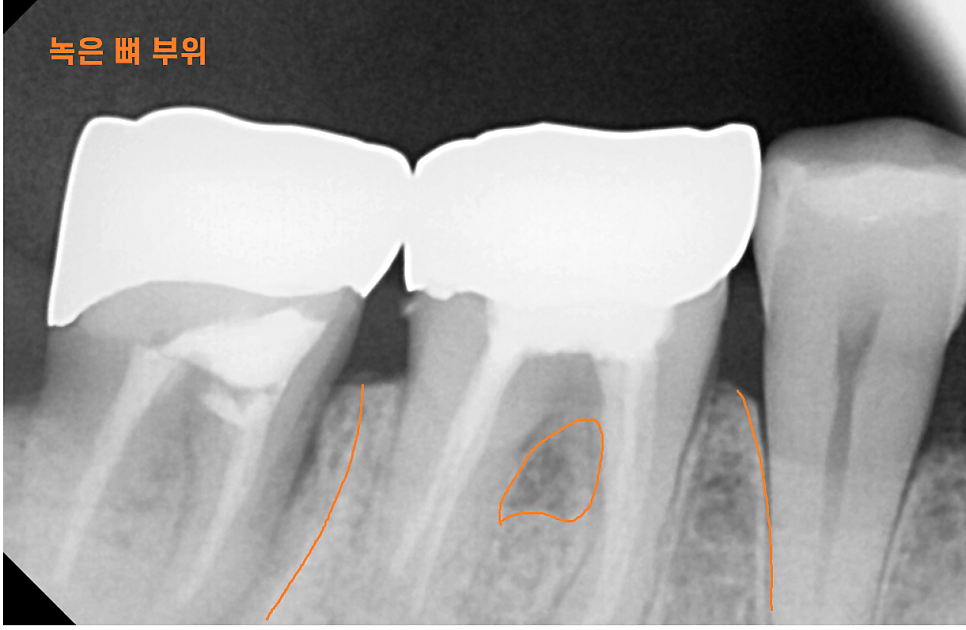

x-ray를 보여드려도 체감을 잘 못하세요~

평면 x ray보다 사실적인

3d ct를 보여드리겠습니다.

뼈는 하얗게 보여야하는데요.

뿌리 염증으로 잇몸뼈를 녹이면

까맣게 변합니다.

뼈가 그만큼 없어지니까요~

치아뿌리 염증 통증은 없더라도 이 염증이 자꾸만 확산되는데

추후 임플란트 치료를 할 때

더 많은 뼈 이식이 필요해요~

당연히 임플란트 예후에도 좋진 않겠죠ㅠㅠ

염증을 제거하고 뼈이식을 하고

공사가 더 커지기도 하고요.